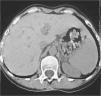

La hipertensión arterial secundaria a hiperaldosteronismo primario es poco frecuente, pero es una enfermedad curable, por lo que nos parece interesante presentar un caso. Se trata de una paciente que inicia un cuadro de hipertensión arterial severa y que recibe tratamiento con diuréticos y fármacos inhibidores de la enzima de conversión de angiotensina (IECA) antes de ser hospitalizada. Cuando la vemos presenta hipopotasemia. A pesar de los suplementos de potasio y de retirar el tratamiento diurético y los IECA, persistía la hipocaliemia, por lo que se inició estudio de hipertensión arterial secundaria. Las concentraciones de renina estaban suprimidos con elevación de la aldosterona. Se realizó una tomografía abdominal que mostró la presencia de un tumor bien delimitado en suprarrenal izquierda, compatible con síndrome de Conn. Tras el hallazgo se resecó el tumor por vía laparoscópica y la anatomía patológica fue de adenoma suprarrenal. Posteriormente, las cifras de potasio y presión arterial se han normalizado sin tratamiento.

Primary aldosteronism resulting from an adrenocortical adenoma is an uncommon but potentially curable form of hypertension. We present the case of a 49-year-old woman that initiated with severe hypertension that was treated with diuretics and ACE inhibitors before being hospitalized. When she came to consult, she had hypokalemia. This persisted in spite of administering potassium supplements and discontinuing the diuretics and ACE secuninhibitors. Therefore, a study was made regarding secondary arterial hypertension. Plasma renin activity was suppressed and aldosterone levels were elevated. Computed tomographic scanning detected a well-delimitated mass in left adrenal gland, suggesting Conn's syndrome. Laparoscopic adrenalectomy was performed and microscopy findings were consistent with aldosteronoma. After surgery hypertension was resolved and potassium levels remained normal.